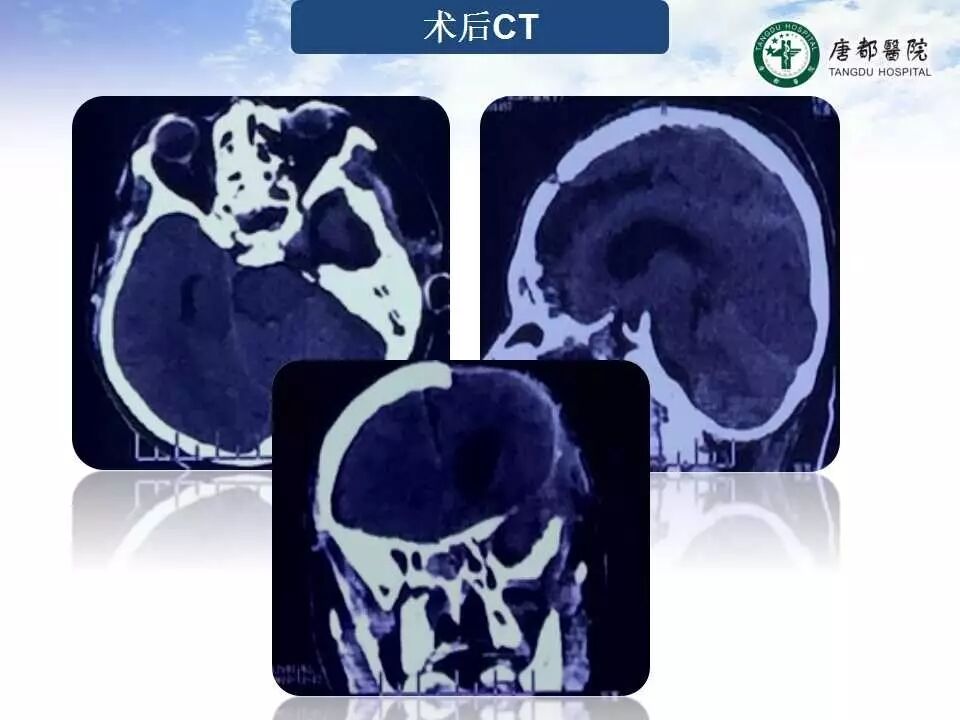

Case 1